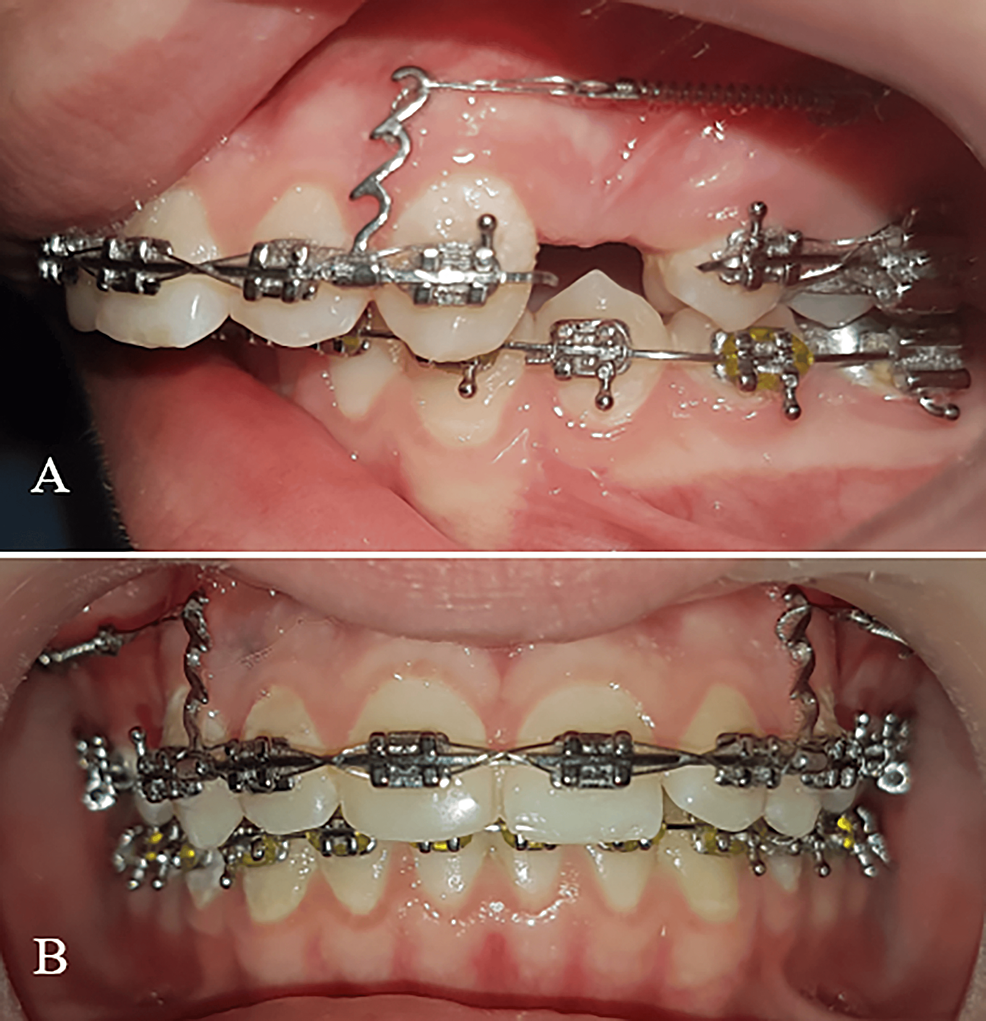

Power arm based space closure. (a) En masse retraction of anterior Retraction Of Anterior Teeth Since there was movement of the posterior segment in both techniques, using er should be considered for closing the extraction. The anterior alveolar bone defines the boundary for the retraction of the anterior teeth in orthodontic treatment. These screws have many clinical applications, such as canine retraction, en masse retraction of all anterior teeth together, intrusion of anterior and posterior. Retraction Of Anterior Teeth.